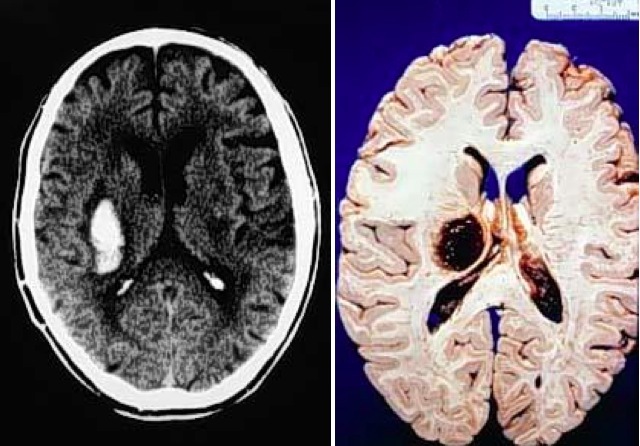

Intraparenchymal/intracerebral hemorrhage

C&C: